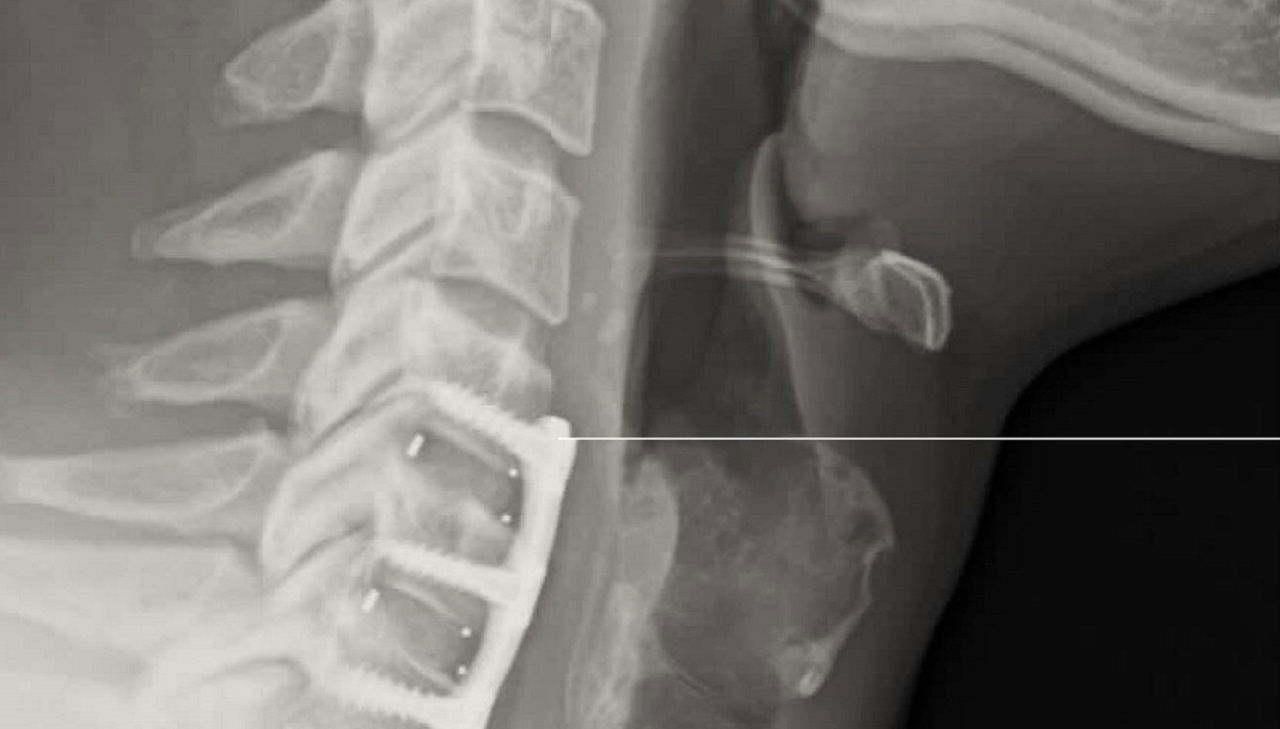

Will Ospreay’s recovery from neck surgery appears to be progressing well, according to a new update from the Body Alignment Clinic in the UK.

The clinic posted an update on Saturday noting that Ospreay is “doing great” six weeks after undergoing neck surgery in mid-September. The post included the caption “Jan 2026”, which appears to indicate the possible timeframe for his in-ring return.

“AEW Allstar Will Ospreay six weeks post op and doing great! Still some way to go with but we’re on the right road,” the statement began. “Jan 2026. Don’t Try This At Home!”